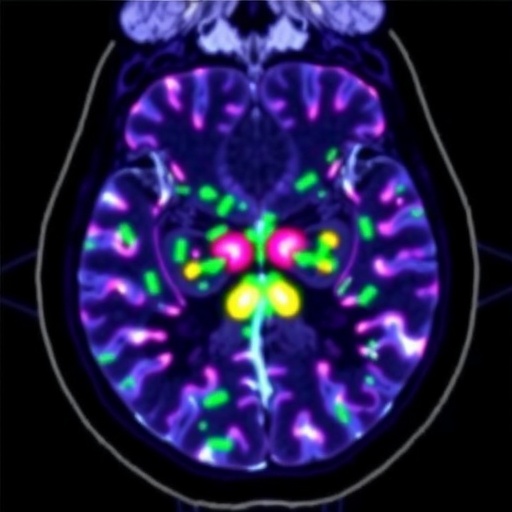

The mannose pathway’s significance lies in its contribution to N-glycosylation, an essential post-translational modification where mannose residues are attached to proteins, influencing their folding, stability, and signaling functions. Defects in this glycosylation can drastically alter cellular homeostasis and fate. The research team employed a sophisticated genetic engineering approach to decouple the mannose pathway from glycolysis, enabling them to manipulate mannose flux independently of glucose levels. This strategy allowed a precise dissection of how varying mannose availability impacts cell survival and signaling networks when glucose is limited.

Their experiments revealed a critical threshold of mannose pathway activity that dictates cell fate. A moderate reduction in mannose metabolism impaired N-glycan biosynthesis, triggering adaptive pro-survival signaling within the endoplasmic reticulum (ER), the cellular organelle responsible for protein folding and transport. Remarkably, these stress responses were initiated without compromising immediate cell viability, suggesting a finely tuned balance between metabolic flux and cellular adaptation.

When mannose pathway activity was further diminished to minimal levels that still permitted survival, the researchers observed a depletion of the lysosomal glycocalyx—a protective glycan-rich layer cushioning lysosomal membranes. Given that lysosomes play a pivotal role as the cell’s recycling centers, maintaining their integrity is paramount. The loss of glycocalyx exposed lysosomal membranes to destabilization, which markedly increased the risk of lysosomal rupture and consequential cell death, highlighting a vulnerable node in cancer cell metabolism during glucose scarcity.

Mechanistically, the team demonstrated that the low metabolic flow of glucose into the mannose pathway precipitated these cellular alterations through defects in N-glycosylation processes. This cascade effect underscores the mannose pathway’s pivotal role as a metabolic sensor, linking nutrient availability to quality control and survival signaling machinery. The activated pro-survival pathways in the ER serve as an adaptive lifeline, enabling cancer cells to endure and thrive amidst nutrient stress.